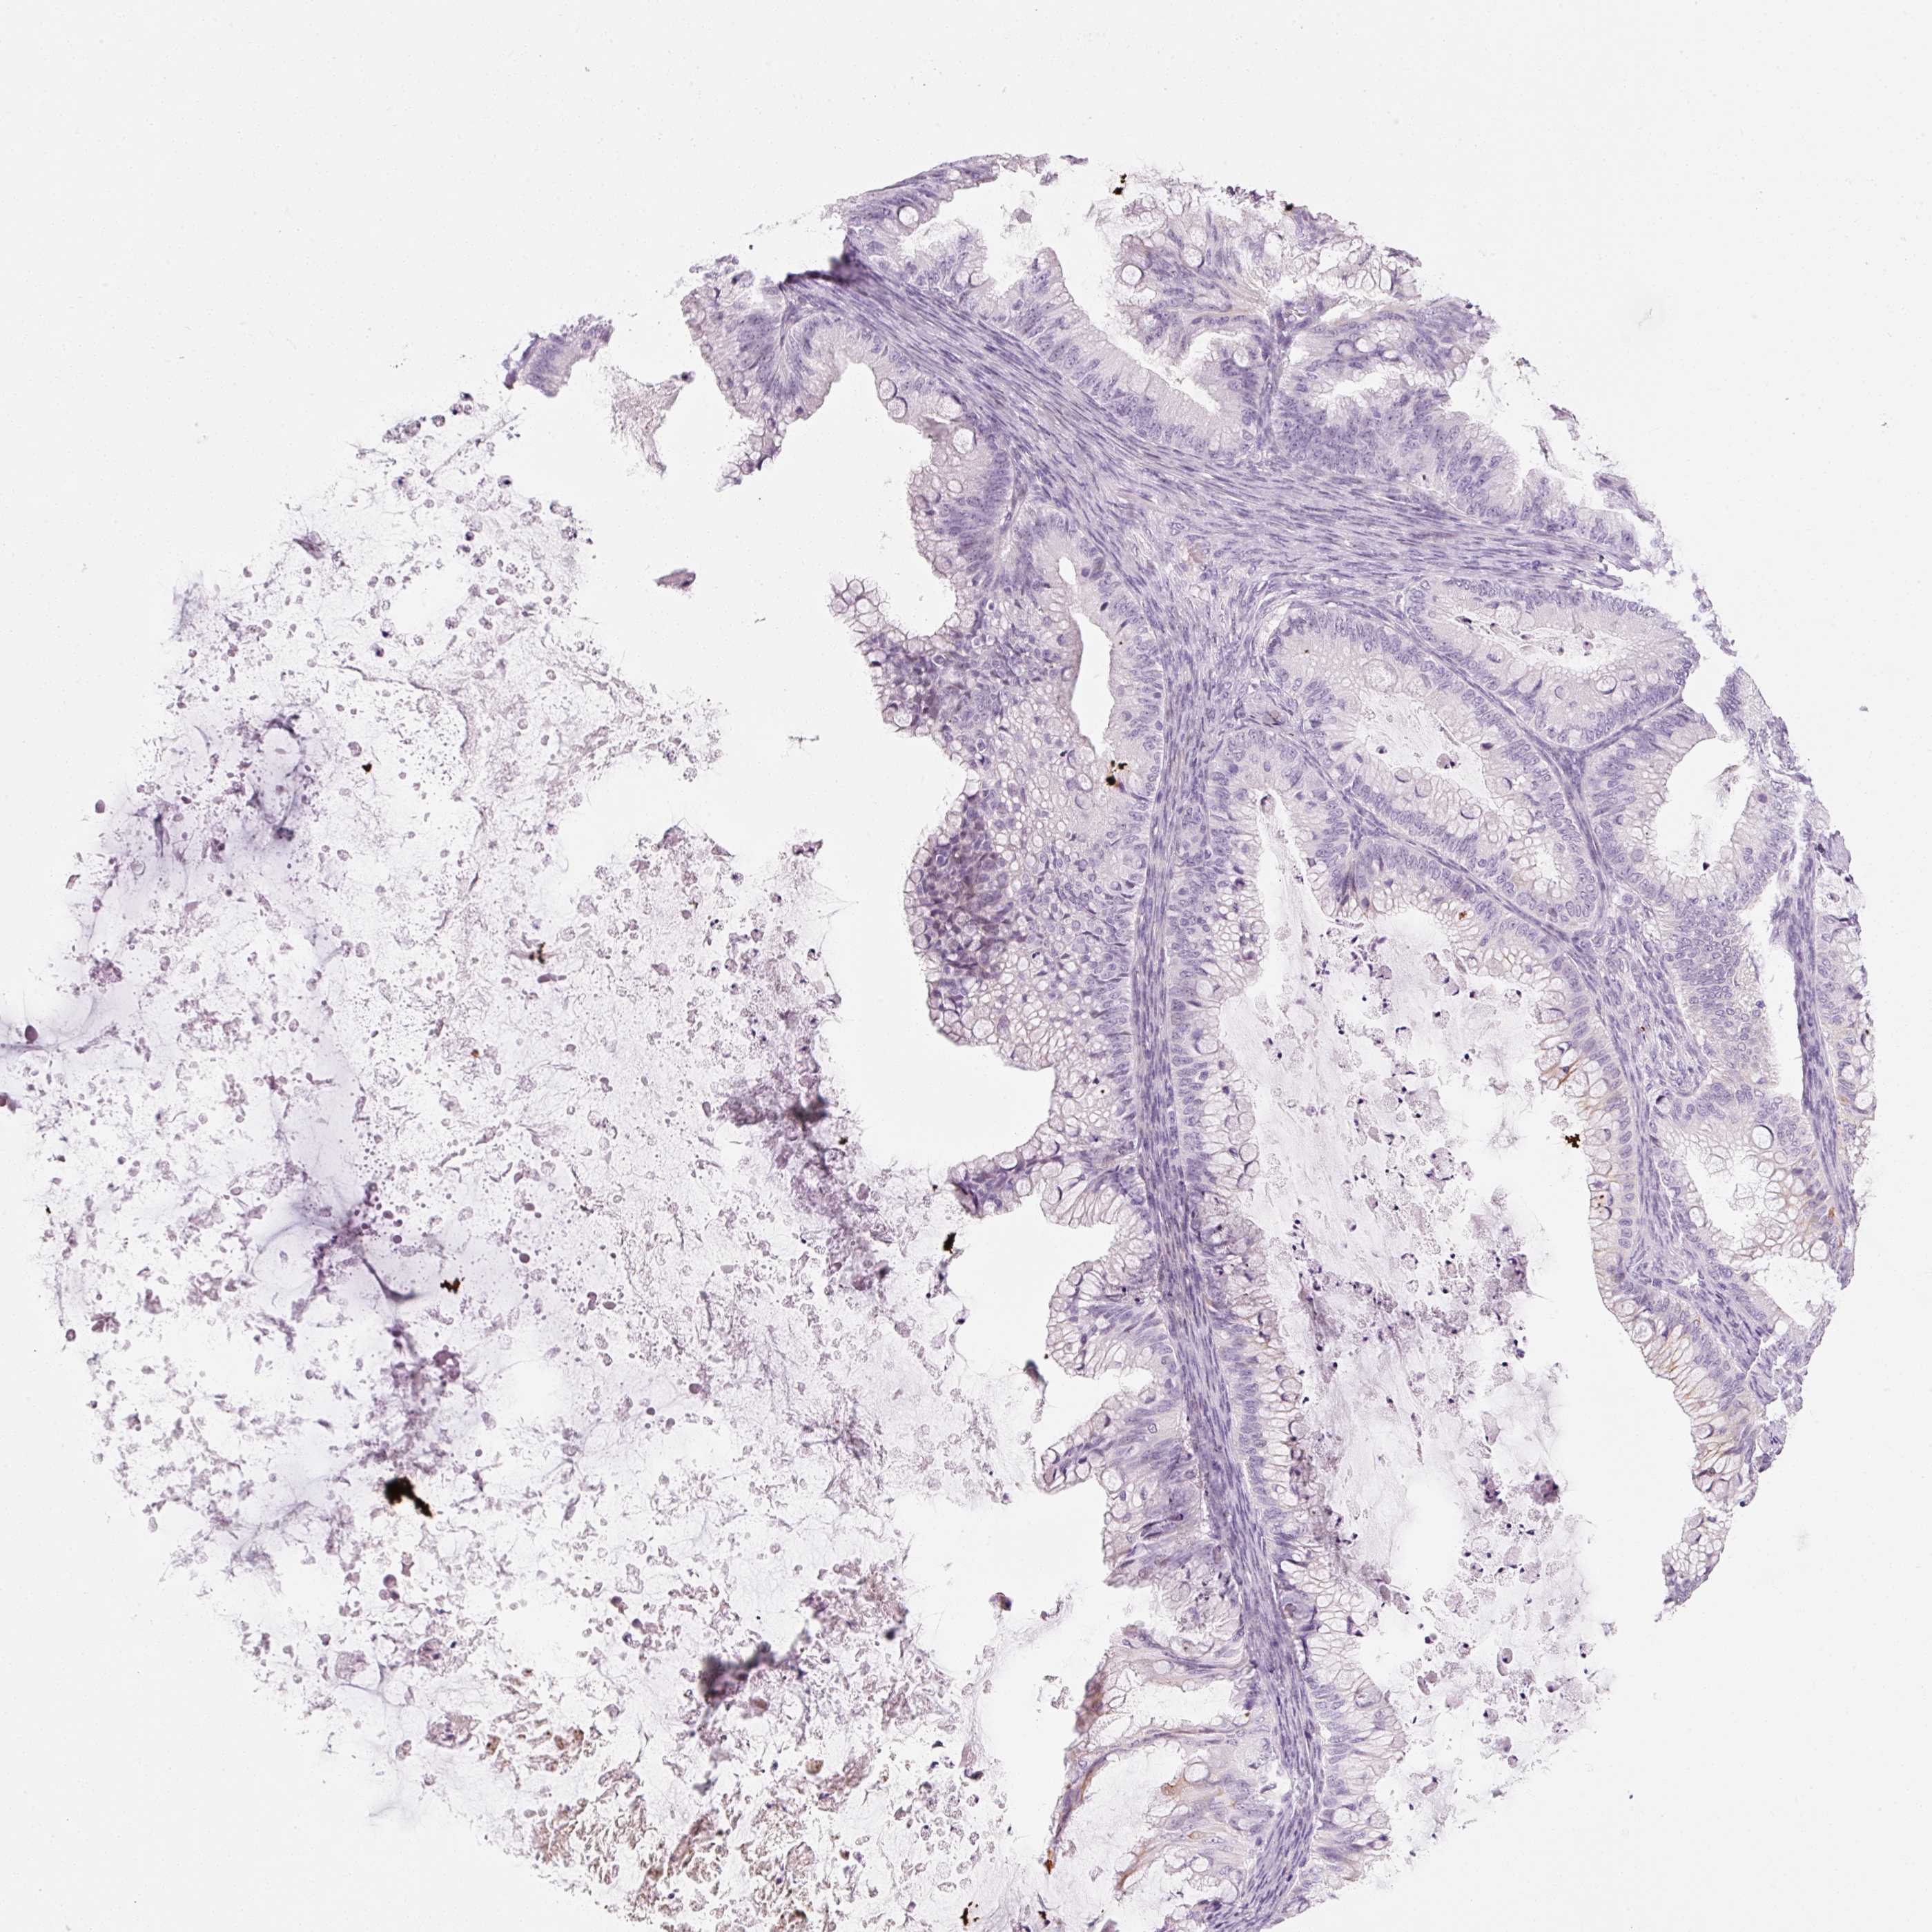

OVARIAN CANCER - Protein expressioni

A mouse-over function shows sample information and annotation data. Click on an image to view it in a full screen mode. Samples can be filtered based on level of antibody staining by selecting one or several of the following categories: high, medium, low and not detected. The assay and annotation is described here.

Note that samples used for immunohistochemistry by the Human Protein Atlas do not correspond to samples in the TCGA dataset.

Antibody stainingi

Antibody staining in the annotated cell types in the current human tissue is reported as not detected, low, medium, or high, based on conventional immunohistochemistry profiling in selected tissues. This score is based on the combination of the staining intensity and fraction of stained cells.

Each image is clickable and will lead to virtual microscopy that enables deeper exploration of all samples and also displays staining intensity scores, fraction scores and subcellular localization as well as patient and tissue information for each sample.

Cystadenocarcinoma, mucinous, NOS